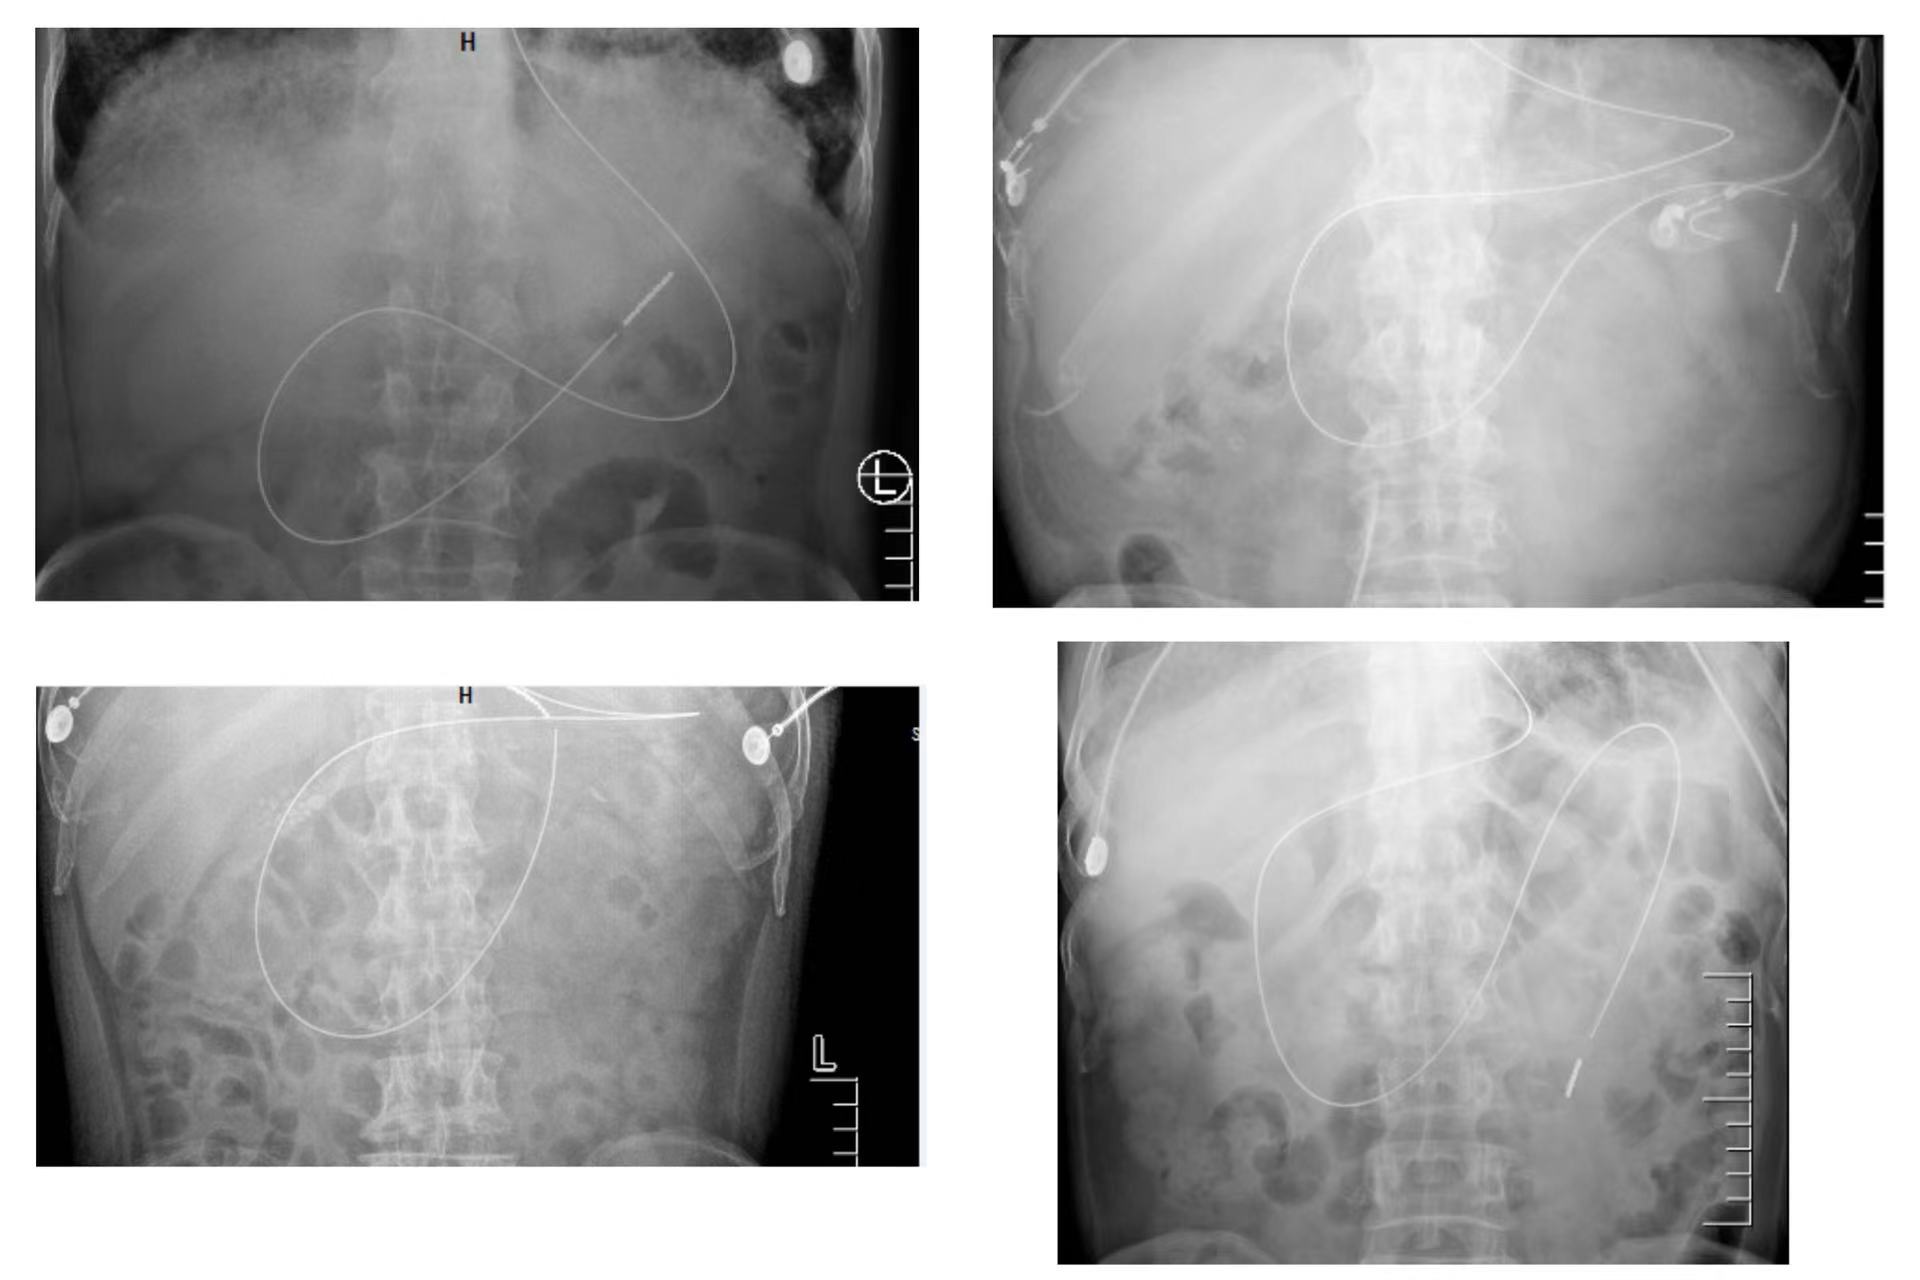

空肠管盲插技术

ICU 里的患者,病情犹如一团错综复杂的乱麻,每一个细微的决策与操作都牵一发而动全身。去年 9 月,徒手盲插空肠管技术在 ICU 悄然开展。

随着经验的不断累积,从去年 9 月至 2025 年 2 月 ,共计完成 9 例徒手盲插空肠管操作。这些成功案例,如同黑暗中的点点星光,为重症患者带来了生的希望,为后续治疗铺就了坚实的道路。